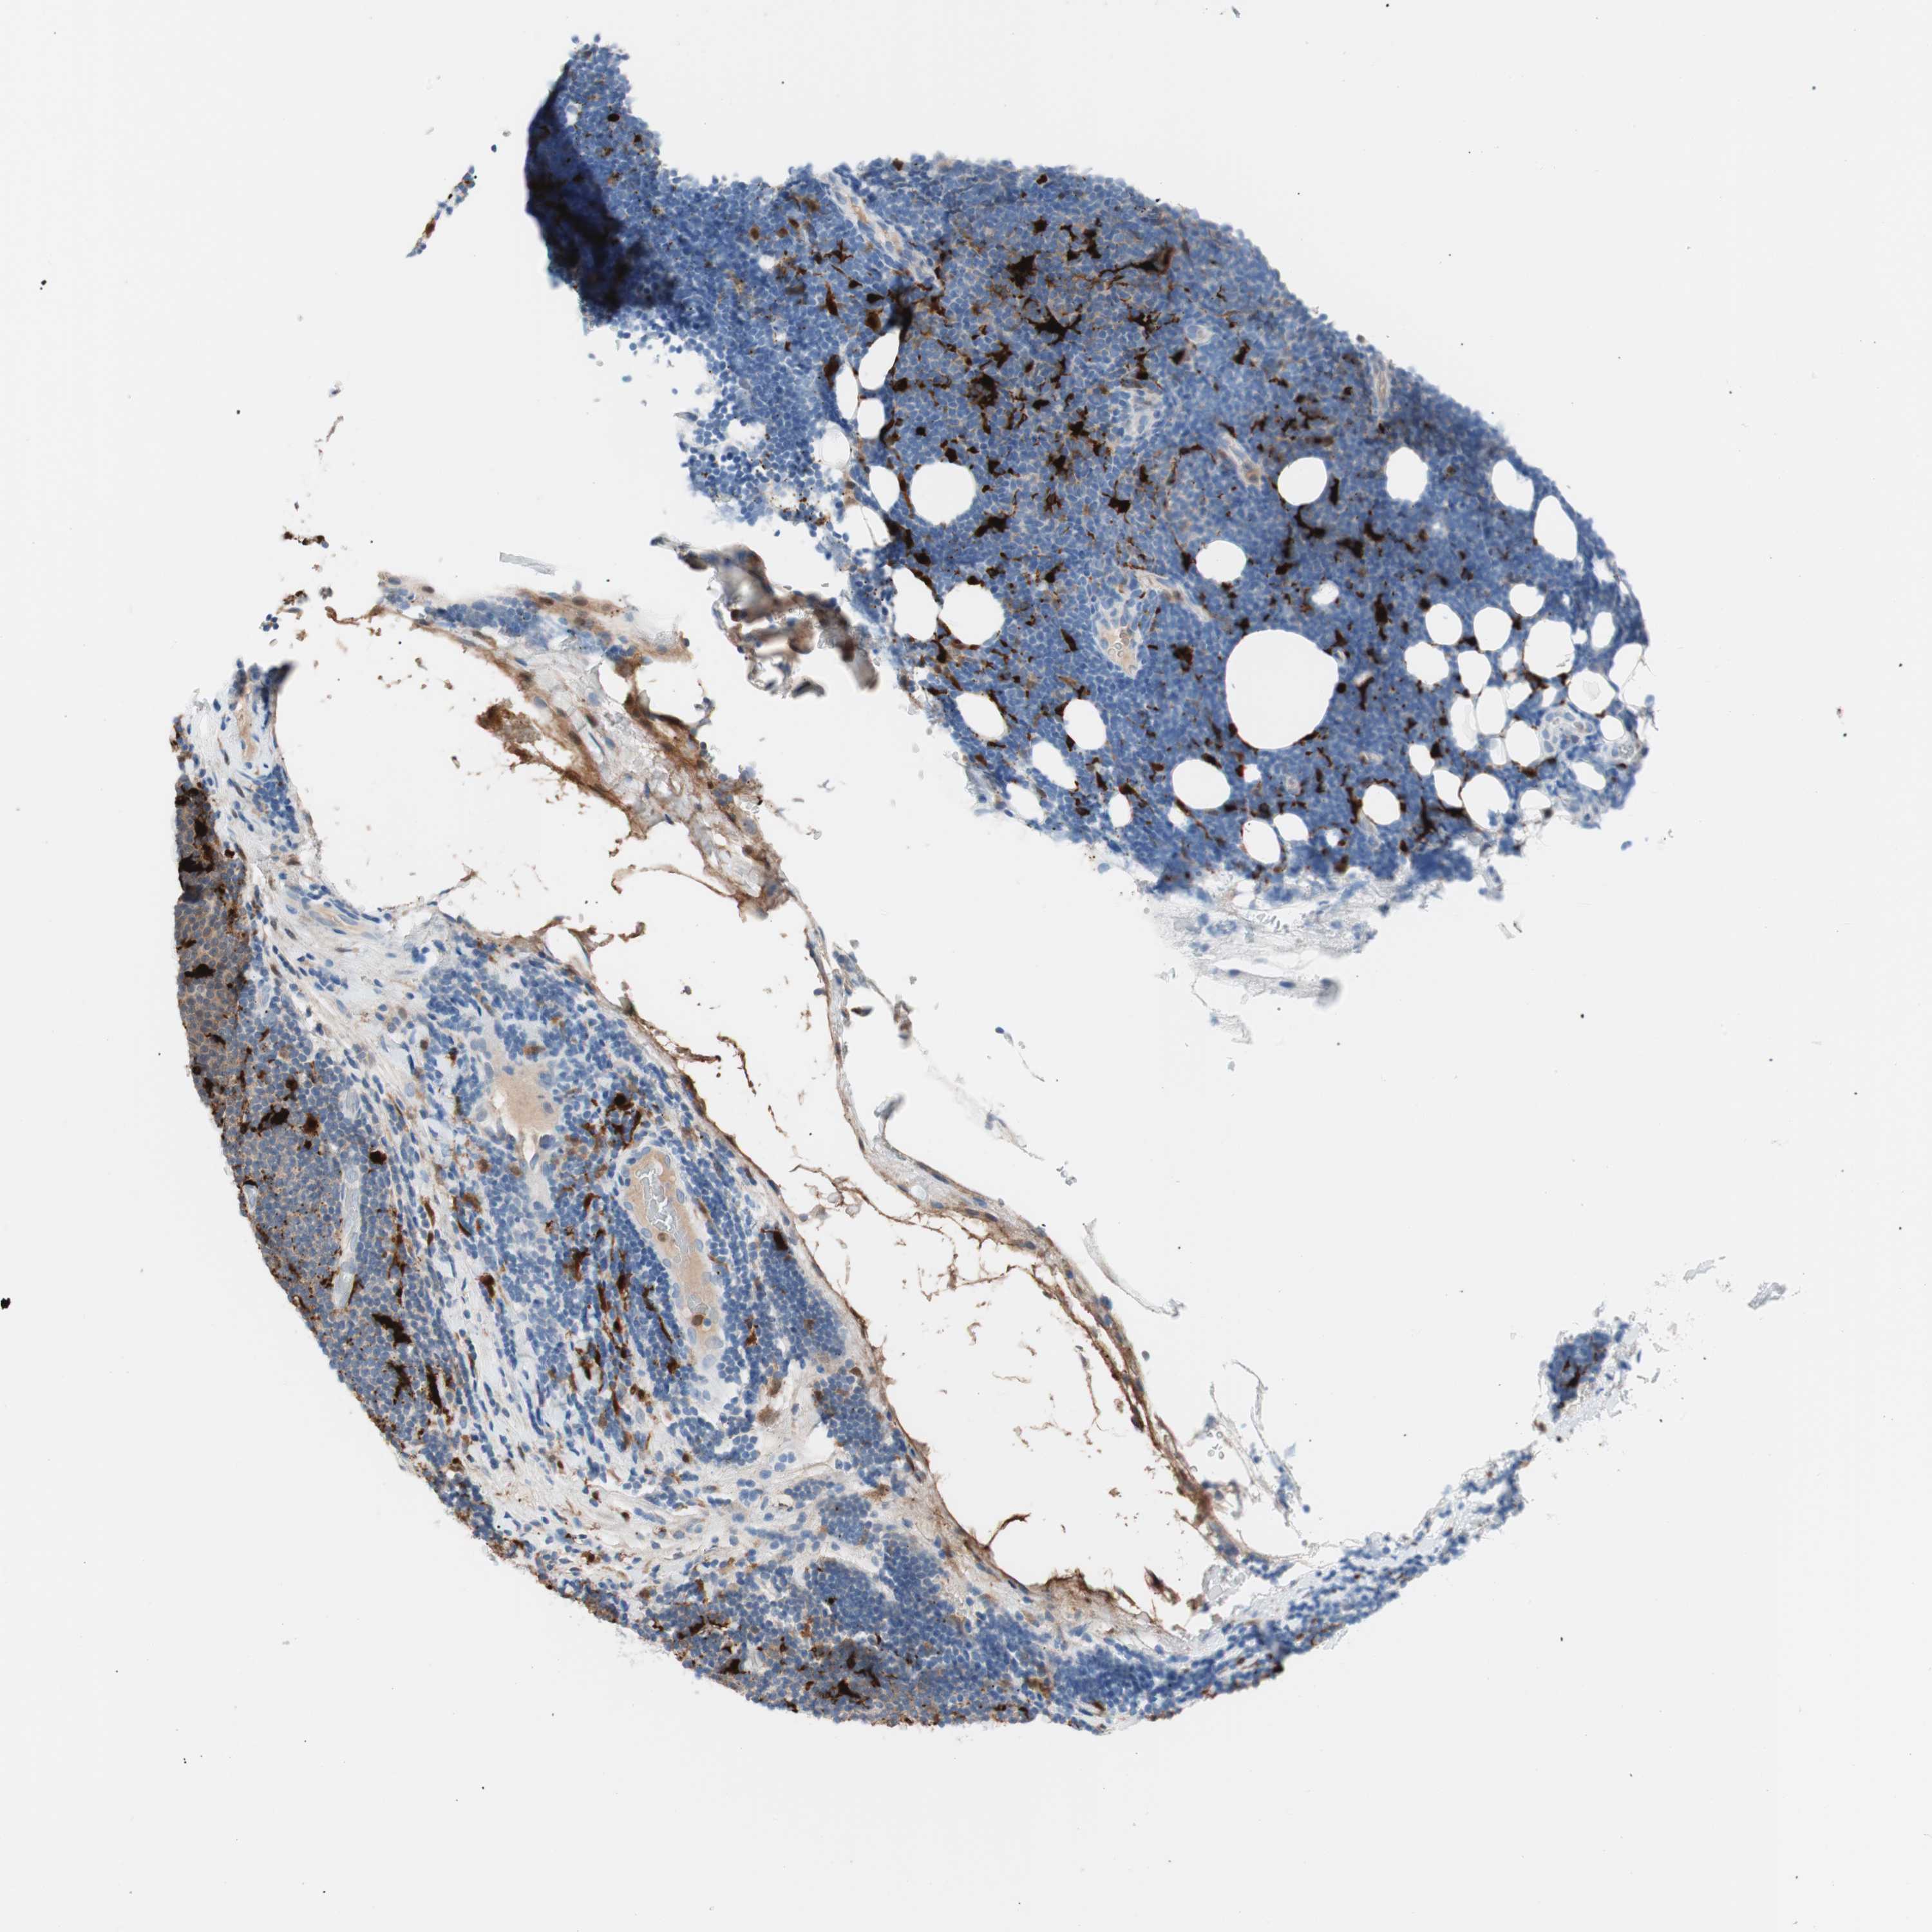

LYMPHOMA - Protein expressioni

A mouse-over function shows sample information and annotation data. Click on an image to view it in a full screen mode. Samples can be filtered based on level of antibody staining by selecting one or several of the following categories: high, medium, low and not detected. The assay and annotation is described here.

Antibody stainingi

Antibody staining in the annotated cell types in the current human tissue is reported as not detected, low, medium, or high, based on conventional immunohistochemistry profiling in selected tissues. This score is based on the combination of the staining intensity and fraction of stained cells.

Each image is clickable and will lead to virtual microscopy that enables deeper exploration of all samples and also displays staining intensity scores, fraction scores and subcellular localization as well as patient and tissue information for each sample.

Antibody HPA003980

Antibody CAB007772

Staining

High

Medium

Low

Not detected

Intensity

Strong

Moderate

Weak

Negative

Quantity

>75%

75%-25%

<25%

None

Location

Nuclear

Cytoplasmic/membranous

Cytoplasmic/membranous,nuclear

Hodgkin's disease, NOS

Malignant lymphoma, non-Hodgkin's type, High grade

Malignant lymphoma, non-Hodgkin's type, Low grade